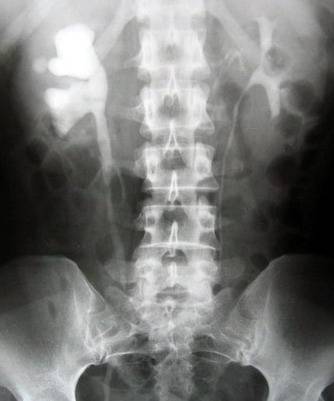

尿路结石是最常见的泌尿外科疾病之一。男性多于女性,约4~5∶1。 尿路结石在肾和膀胱内形成。上尿路结石与下尿路结石的形成机制、病因、结石成分和流行病学有显著差异。上尿路结石大多数为草酸钙结石。膀胱结石中磷酸镁铵结石较上尿路多见。成核作用、结石基质和晶体抑制物质学说是结石形成的三种最基本学说。根据上尿路结石形成机制的不同,有人将其分为与代谢因素有关的结石和感染性结石。细菌、感染产物及坏死组织亦为形成结石之核心。